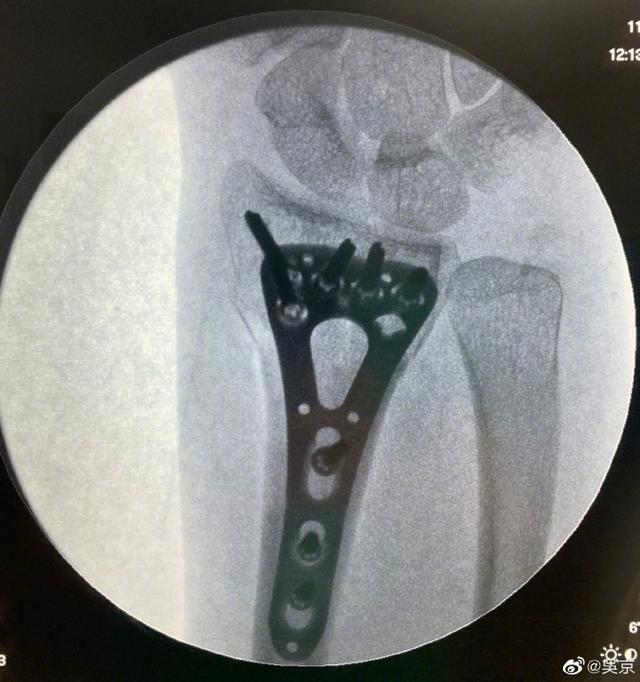

11月10日,吴京在社交平台上晒出谢楠的钢钉照,还调侃说:"二师妹成功的把手中的钉耙像金箍棒一样变进了自己的身体里",语调轻松,可照片却吓坏了一众网友。

照片中,一个巨大的金属支架被固定在骨头上,上面还有好几个长长的钉子,颇有点毛骨悚然的感觉,虽然知道谢楠做手术肯定是麻醉状态下做的,可还是看着都让人觉得疼。